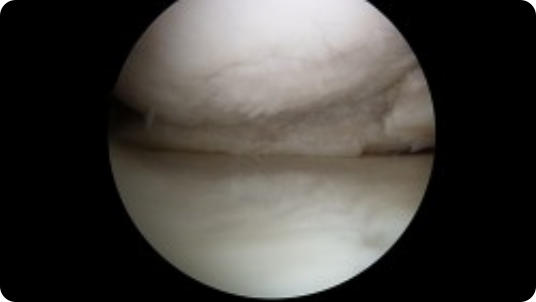

This page contains arthroscopic and radiography images of joint injuries and conditions, and the surgical repairs performed by Dr. Joshua Landau.

Arthroscopic image of a miniscus tear Arthroscopic image of a miniscus tear after knee arthroscopy Arthroscopic image of a bone spur Arthroscopic image of a removed bone spur Arthroscopic image of a shoulder dislocation Arthroscopic image of a repaired shoulder dislocation Arthroscopic image of a rotator cuff tear Arthroscopic image of a repaired rotator cuff